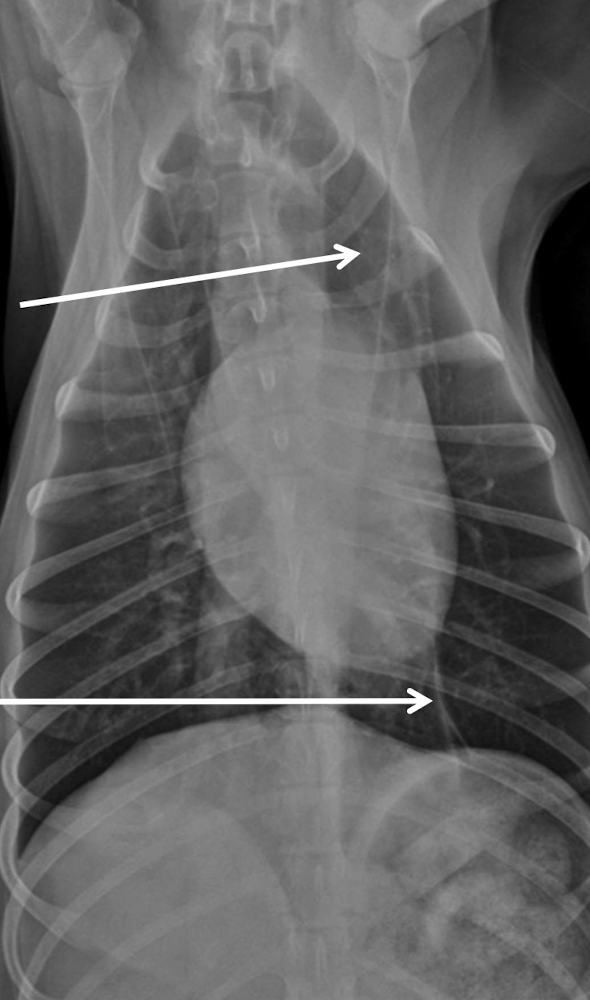

which one pulmonary mass vs extrapleural sign

A

extrapleural sign:

Broad-based mass on the chest wall

Convex shape

Lungs displaced medially

+/- Uneven distances between ribs